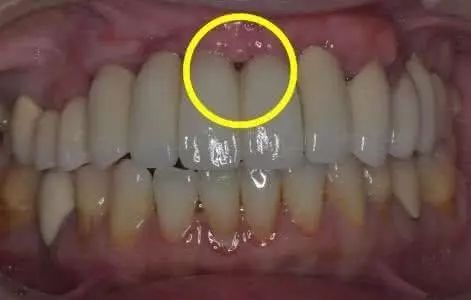

牙周炎示意圖